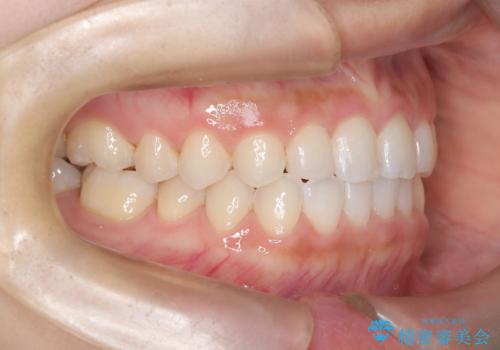

- 前歯の凸凹を主訴に来院された患者様です。

カウンセリング時に、側切歯が矮小歯であることを指摘したところ、適切な幅径での修復を希望されました。

インビザラインを用い、計画通りに歯並びを改善することができました。

矮小歯の幅径を大きくすることで、より理想的な噛み合わせを作ることができます。